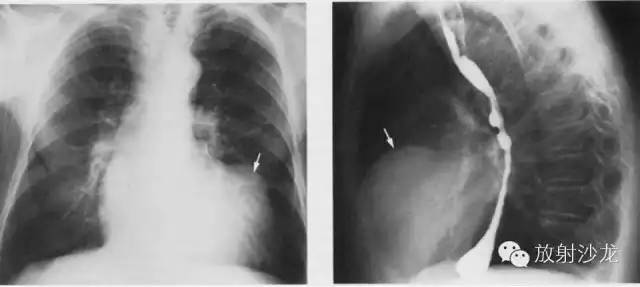

不同程度的左房增大

1、后前位:心尖左、下移位(胃泡内、越出锁骨中线)相反搏动点上移,左心缘延长、圆隆并向左下扩大。

2、左前斜位:心后缘向后下延伸与脊柱重叠,室间沟前下移。

3、侧位:食道前间隙消失,心后间隙变窄。